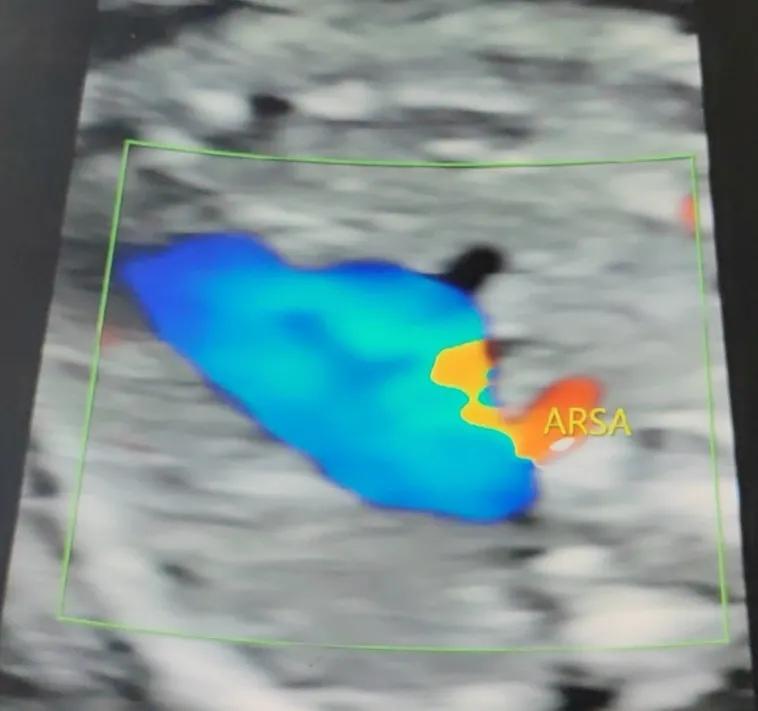

胎儿右锁骨下动脉迷走就是本该从头臂干发出来的右锁骨下动脉直接从主动脉弓发出来,沿着气管后方往右侧腋下延伸。因此,被称为右锁骨下动脉迷走。本来,一根小血管直接从大血管发出并不是坏事情,毕竟血供会更丰富,但是血管走的路线却是让人担忧的,其是从气管后方经过,似乎对气管有束缚压迫作用。因此,我们会担心会不会存在压迫,引起窒息等。

超声实图

右锁骨下动脉迷走